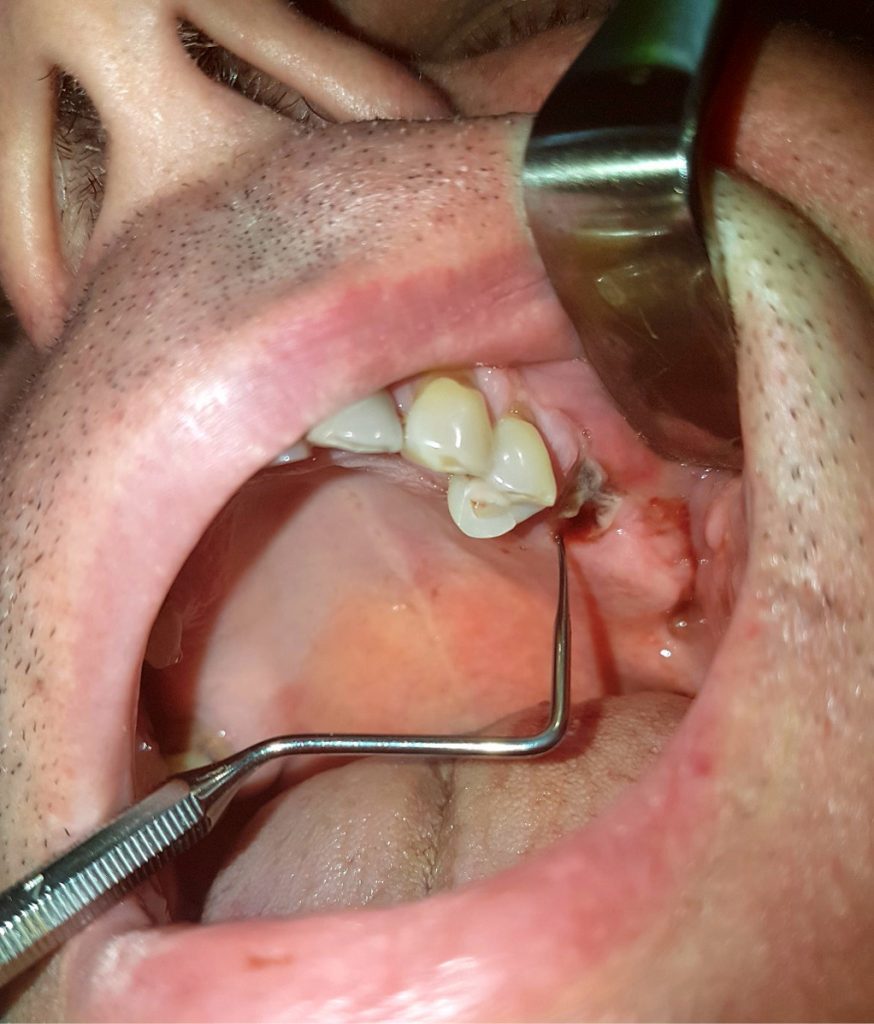

STRESZCZENIE: Artykuł prezentuje przypadki miejscowych powikłań, które mogą się zdarzyć w trakcie ekstrakcji zębów. Jak każda procedura chirurgiczna, usunięcie zębów jest obarczone ryzykiem różnorodnych powikłań i komplikacji. Wśród nich wyróżniamy: krwawienie poekstrakcyjne, połączenie ustno-zatokowe, uszkodzenie nerwów, infekcje i wiele innych.

W dziedzinie, jaką jest chirurgia stomatologiczna, często można spotkać się z występowaniem powikłań, które są rozumiane jako nieprawidłowości będące następstwem procedur medycznych. Należy brać pod uwagę ich występowanie podczas każdego zabiegu chirurgicznego. Zabieg chirurgiczny w jamie ustnej niesie ze sobą szereg powikłań śród- i pooperacyjnych. Powikłania jatrogenne mogą powstać w czasie wykonywania standardowych i z pozoru nieskomplikowanych operacji, takich jak ekstrakcja zęba. Mogą dotyczyć zarówno samego zabiegu, jak i przygotowania do jego przeprowadzenia podczas wykonywania znieczulenia miejscowego (1, 2). Każde usunięcie zęba powinno być poprzedzone dokładnym badaniem klinicznym, wywiadem medycznym, ustaleniem wskazań i przeciwwskazań do zabiegu oraz określeniem stanu zęba i okolicznych tkanek. Tylko wtedy stomatolog może zminimalizować [...]